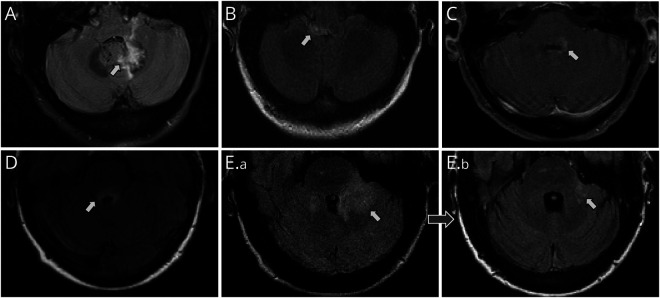

Results: From 432 patients with AQP4+NMOSD, we identified 17 (4%) with cerebellar attacks. The median age at attack onset was 47 years (range, 7-74). Cerebellar symptoms and signs were noted in 16 (94%) of 17 and the remaining patient was intubated preventing a detailed cerebellar exam. The median Expanded Disability Status Scale score at nadir was 5 (range, 2-9.5). Sixteen (94%) had other regions involved during the attack, most frequently with brainstem or area postrema involvement. Cerebellar MRI T2-lesions (8 single; 11 contiguous with the brainstem; 6/15 [35%] enhancing) were located in cerebellar peduncles, 15 (inferior, 5; middle, 10; superior, 10), and cerebellar parenchyma, 8 (dentate, 4; medial, 2; lateral, 4). T2-lesions persisted in 9 (82%) of 11 beyond 6 months.

Discussion: Cerebellar involvement during attacks of AQP4+NMOSD is rare but the associated neurologic deficits tend to be severe. Cerebellar peduncle or dentate nucleus T2-lesions are frequent MRI accompaniments. Clinical features and MRI lesion patterns of cerebellar involvement could be incorporated into future iterations of AQP4+NMOSD criteria.